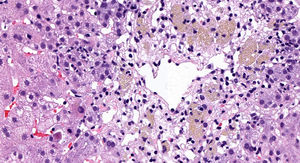

Presentamos el caso de una mujer de 55 años que ingresó en Otorrinolaringología por un cuadro de sordera súbita sin causa aparente. Se inició tratamiento empírico con 3 dosis de corticoides intratimpánicos y 500mg de metilprednisolona iv/24horas durante 7 días (dosis total acumulada de 3,5g), con posterior pauta descendente oral de deflazacort. Siete semanas más tarde comenzaba con prurito y coluria acompañados de elevación de las pruebas de función hepática (AST 205 U/l, ALT 533 U/l, FA 102 U/l, GGT 118 U/l), que aumentaron progresivamente en las siguientes semanas, con marcada citólisis (AST 858 U/l y ALT 1468 U/l), alcanzando una bilirrubina máxima de 3,5mg/dl. La paciente no tenía antecedentes de hepatopatía previa ni de consumo de alcohol. Las serologías para virus hepatitis A, B, C y E fueron negativas, así como el herpes virus, varicela zóster, Epstein Barr o citomegalovirus. Únicamente presentó positividad para anticuerpos anticitoplasma de neutrófilo (ANCA P1/640), el resto de autoinmunidad (anticuerpos antinucleares, anti-DNA nativo, antimitocondriales, antimúsculo liso y anti-LKM) fueron negativos. Asimismo presentaba valores normales de inmunoglobulinas y un perfil electroforético normal. La ecografía abdominal solo mostraba colelitiasis. Ante la elevación persistente de transaminasas se realizó un ensayo terapéutico con 60mg de prednisona oral por sospecha de un comienzo de hepatitis autoinmune seronegativa, que se descartó posteriormente con el resultado de la biopsia hepática (fig. 1). Finalmente, una vez excluidas las causas virales e inmunológicas y tras establecer la relación temporal causa-efecto, con un valor de 6 puntos en la escala CIOMS/RUCAM se determinó como origen de la hepatitis el tratamiento «en bolus» con metilprednisolona. Actualmente tras 7 meses del inicio del cuadro presenta normalización analítica.

El curso clínico puede variar desde una hipertransaminasemia asintomática2,3, que es lo más frecuente, hasta un fallo hepático fulminante4. Su periodo de aparición varía desde unos días hasta varias semanas. Los hallazgos histológicos descritos con este fármaco son variables, aunque predominan los datos de necrosis hepatocitaria e inflamación (tabla 1).